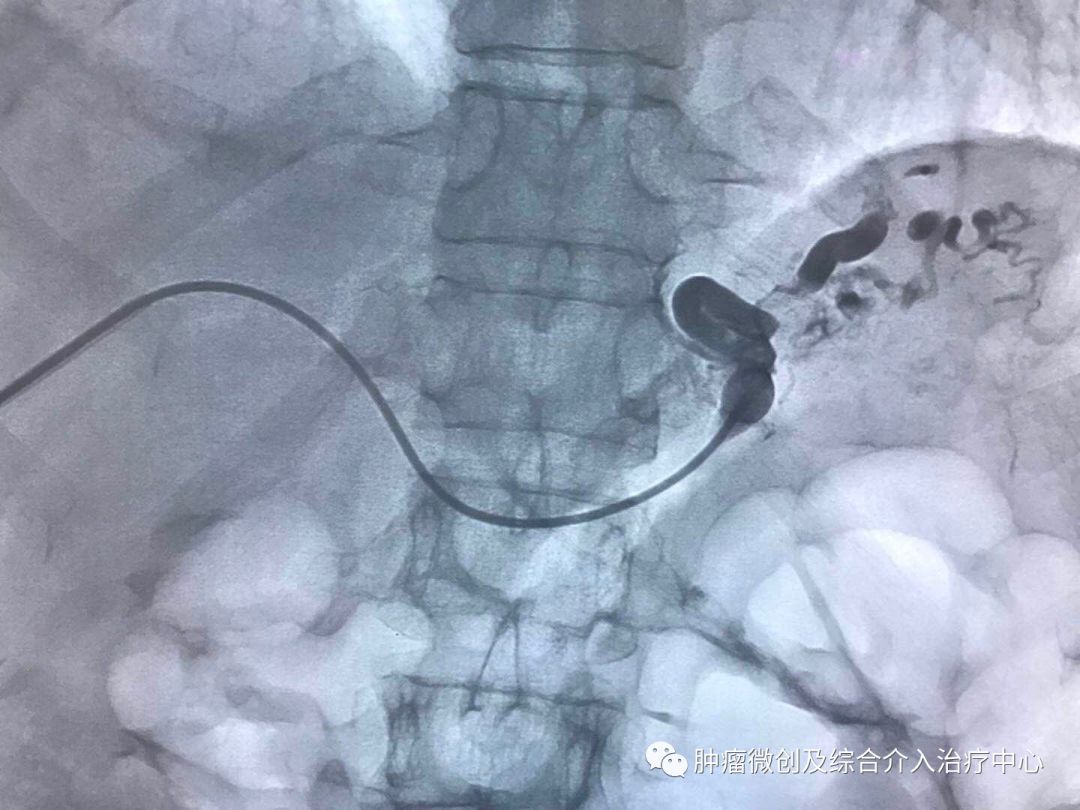

(经皮穿肝-门静脉穿刺成功,门脉高压,门静脉扩张明显)

(食管胃底静脉栓塞术,在血管根部将破裂的上消化道出血血管栓塞完全,即可止血)项目简介:肝硬化门脉高压失代偿期临床表现为反复消化道出血等,患者一般情况欠佳,传统治疗难以改善。食管胃底静脉+胃冠状静脉栓塞术暨经皮肤穿门脉食管胃底+胃冠状静脉栓塞明显降低因消化道大出血导致休克及死亡的风险; 结合内科治疗,其顽固性腹水症状可迅速消退,改善患者生活质量。10肝硬化门脉高压失代偿介入治疗(TIPS术)